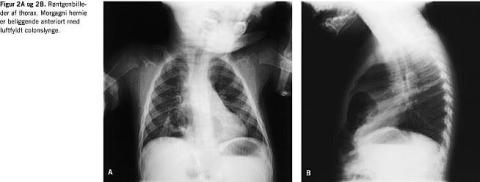

På børneafdelingen på Amtssygehuset i Glostrup har vi igennem de seneste to år diagnosticeret to tilfælde af sent debuterende medfødt diafragmahernier, patient nummer 4 i Tabel 1 (Figur 1A og 1B) samt patient nummer 3 i Tabel 2 (Figur 2A og 2B).

Sent debuterende medfødt diafragmahernie er ikke en statisk tilstand og kan variere i sværhedsgrad og debutere i forbindelse med barnets vækst, fysisk aktivitet og øget intrabadominalt tryk, f.eks. hoste. Flere patienter har haft normale røntgenbilleder af thorax forud for symptomdebuten [5, 13, 16]. De radiologiske fund kan variere for den enkelte patient pga. varierende hernieindhold og pga. spontan remission [7, 17]. Røntgenologisk er sent debuterende diafragmahernie blevet tolket som pneumonia, aspiration af fremmedlegeme, cyster, pneumothorax, tumor og pleuraeffusion [2, 7-9, 11-13, 17, 18]. Dette har ledt til, at man ofte har foretaget flere forskellige diagnostiske tiltag for den samme patient, blandt andet røntgenundersøgelse af øsofagus og colon, CT og MR-skanning af thorax, ultralydskanning af abdomen, bronkoskopi med bronkial lavage og pyelografi [2, 6, 7, 9, 10]. I et ønske om at diagnosticere et diafragmahernie er der anbefalet en simpel røngtenundersøgelse af thorax suppleret med nedlæggelse af en nasogastisk sonde [7, 10]. I flere undersøgelser, hvor man ikke har brugt nedlæggelse af en nasogastrisk sonde, har man fundet, at colonindhældning er effektiv. Bariumindhældning kan dog lede til underdiagnosticering, da bariums hydrostatiske kræfter kan reducere herniet [7]. Desuden er undersøgelsen mere belastende for barnet. Den anbefales derfor først, hvis man efter røntgenundersøgelse af thorax med nedlæggelse af en nasogastrisk sonde fortsat er i tvivl om, hvorvidt barnet har et diafragmahernie eller ej. Tilsvarende kan røntgenundersøgelse af øsofagus og øsofagoskopi eventuelt anvendes diagnostisk i disse situationer. I hvert enkelt tilfælde må man overveje, hvilket diagnostisk tiltag der forventes at være den bedste undersøgelse nr. to.